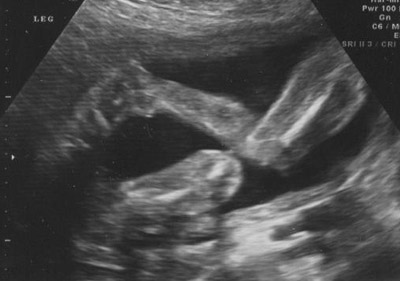

Legs and feet: